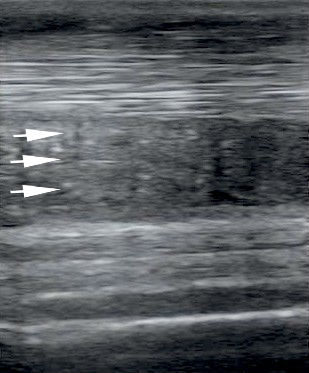

A betegséget ultrahanggal diagnosztizáljuk. Fontos, hogy a sérülés kialakulása után legalább két hetet várjunk a végleges diagnózis felállításával, mert gyakori, hogy az ultrahangos kép még tovább romlik ez alatt az idő alatt, és a túl korán végzett ultrahangozással alábecsülhetjük a sérülés mértékét.

Hosszmetszetben vizsgált, sérült járulékos szalag. A szabályos, erős, fehér rostokból álló szerkezet helyett szürke, szemcsés sáv (nyilak)